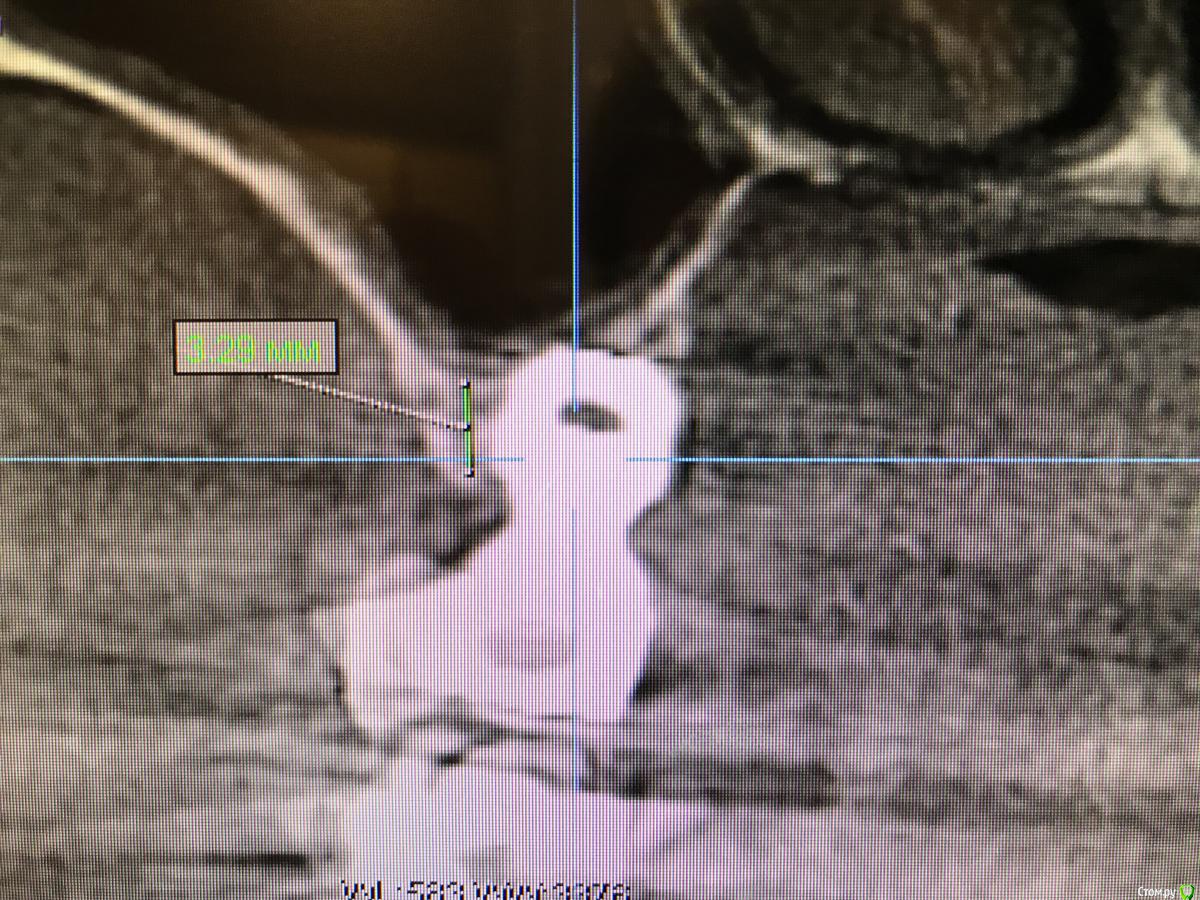

sole13 Опубликовано 26 апреля, 2018 Поделиться Опубликовано 26 апреля, 2018 посоветуйте, пожалуйста недавно удалили 26 зуб. КТ на дату 14 апреля (2, 5 месяца после удаления). Насколько я понимаю, в среднем у меня 6 мм кости. Возможен ли в моем случае закрытый синус лифтинг (а не открытый) и имплант 9 на 5 мм будет достаточен ?( высота и ширина) про достаточность - подразумевается, что конструкция будет выдерживать жевательную нагрузку на протяжении многих лет и при протезировании не будет "лошадиной" коронки. спасибо! Ссылка на комментарий

sole13 Опубликовано 10 августа, 2018 Автор Поделиться Опубликовано 10 августа, 2018 (изменено) уважаемые хирурги, прошу ваш совет 3 месяца назад было сделана имплантация 26 зуба, закрытый синус,сделано повторное свежее КТ через 3 месяца у меня ощущение постоянного комка слизи в носоглотке с момента операции (иногда отплевывается часть и это оч густое содержимое). пила 2 курса синупреда, 2 месяца на море, 2 курса ринофлоимуцила прокапала. если чуть заболеваю, то слева ощущение тяжести в крыле носа как при гайморите. хирург говорит, что перфорации гайморовой нет и в 50% случаях это нормальная реакция гайморовой - выделять слизь, что через месяца 3-4 у меня это пройдет. действительно гайморова пазуха не перфорирована и ощущение слизи -норма? еще меня смущает черная область вверху импланта справа на снимке и черное под имплантом и справа по вертикали - что это? Изменено 10 августа, 2018 пользователем sole13 Ссылка на комментарий